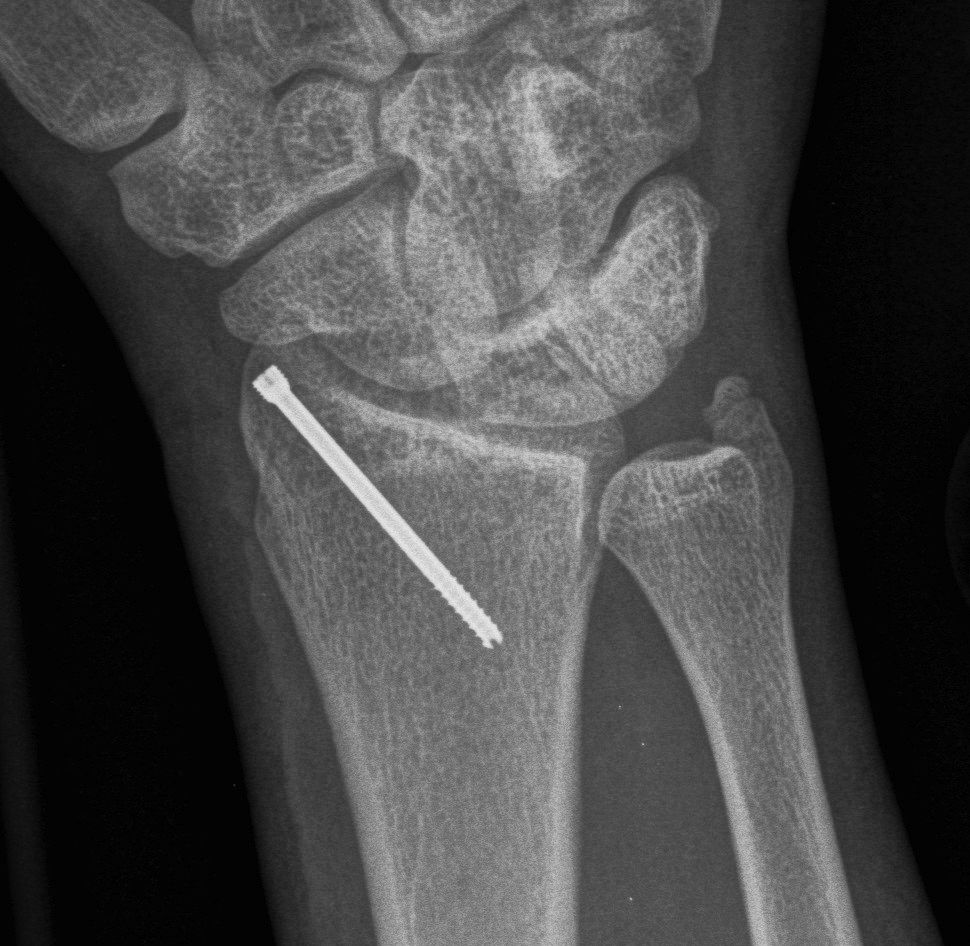

Surgical options

K wires

Volar locking plates

External fixation

Dorsal spanning plates

Distal Radius Fracture K wires APplateex fixbridge plate